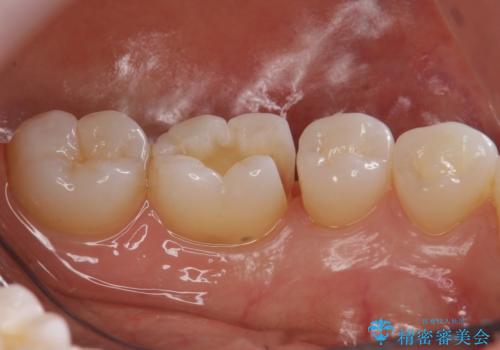

奥歯の虫歯 セラミックインレーでの治療

- 奥歯の黒ずみが気になるとのことで来院されました。

検査の結果、歯と歯の間に小さな虫歯ができていることが確認できました。

白い詰め物をご希望されたため、今回はセラミックインレーでの治療となりました。

黒ずみもなくなり、虫歯も取り切ることができ大変満足していただけました。

虫歯の除去後に適合の良い修復物を装着することは今後の虫歯リスクを減らすことに繋がります。